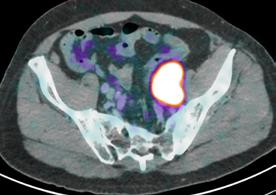

New Developments in PSMA PET Imaging for Prostate Cancer

In the 2020-21 issue of Images, we shared the story of the U.S. Food and Drug Administration’s approval of Prostate-Specific Membrane Antigen (PSMA) PET imaging, based on research conducted at UC San Francisco and UCLA. The technique uses positron emission tomography in conjunction with a PET-sensitive drug that is highly effective in detecting prostate cancer throughout the body so that it can be better and more selectively treated. The PSMA PET scan also identifies cancer that is often missed by current standard-of-care imaging techniques.

In September 2021, a team led by Thomas Hope, MD, at UCSF and Jeremie Calais, MD, at UCLA, published a paper in JAMA Oncology (doi:10.1001/ jamaoncol.2021.3771) detailing the phase 3 diagnostic efficacy trial that led to FDA approval of PSMA PET.

What is the main focus of the JAMA Oncology paper?

The paper focuses on the role of 68Ga-PSMA-11 PET at time of initial staging. The goal was to compare the imaging results to nodes found at time of surgery in order to determine the sensitivity and specificity of PSMA PET. This study showed that PSMA PET has a high specificity for the detection of nodal metastases, although the sensitivity for small pelvic nodes was lower than expected.

Next up is to grow the use of PSMA PET for patient selection in PSMA radioligand therapy.

Currently there are no FDA approved agents for PSMA radioligand therapy, but we expect approval of 177Lu-PSMA-617 in the coming months, and so we will start using PSMA PET in this patient population.  Additionally, now that PSMA PET will be widely available, we will need to complete clinical trials in order to understand how to manage patients better based on the results of PSMA PET imaging studies. 